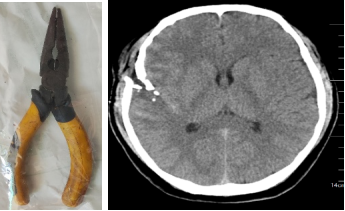

近日,河南籍42岁的张某因意外跌落致使平时工作的钳子插入脑内,情况严峻,随时危及生命。

家属立即将患者送入广州市中西医结合医院急诊科救治,急诊外科医师接诊后第一时间启动急诊绿色通道。

经颅脑外科值班医师会诊诊后,决定马上走绿色通道完成头颅CT并送至手术,颅脑外科江峰主任在收到通知后马上赶回医院,经过急诊、颅脑外科及麻醉科等多学科会诊后,为患者制定了一个安全的“拆弹”方案。

患者头部CT显示钳子穿破颅骨插入脑内近5cm深,周围脑组织有少量出血,一般遇到此种情况,选择的手术方案都是全身麻醉下进行局部切开后拔除钳子,再进行深入的清创止血手术,但这样会对脑部造成二次损伤,颅内损伤面积增大,会导致手术后患者留下严重的后遗症,甚至危及生命。

江峰主任反复阅片并组织科室进行疑难病例术前讨论,认为所幸患者颅内大血管并未伤及,损伤的脑组织位于右侧大脑半球亚功能区,故患者神志仍然清楚,目前无明显神经功能障碍。

与家属及患者充分沟通后决定送手术室在局麻下手术,但做好随时局麻转全麻的准备,以备患者不能配合手术时立即改为全麻。